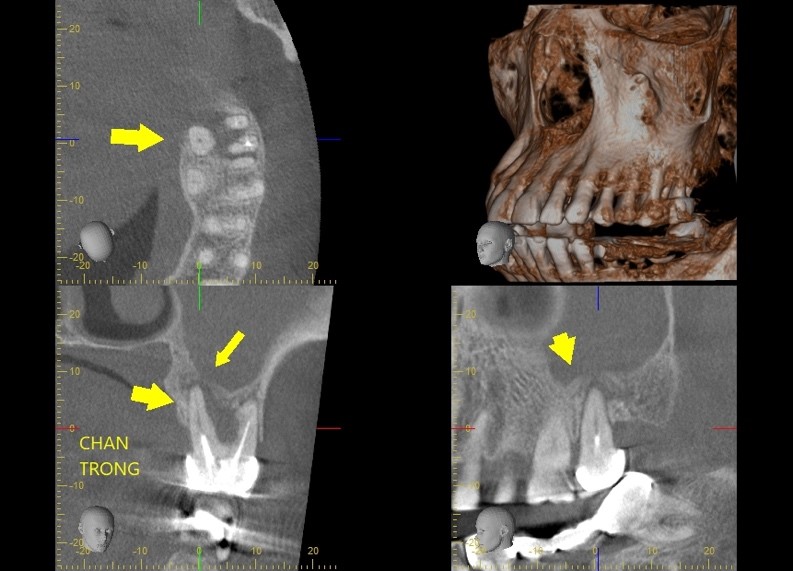

viem xoang 1

Hình 1. Lỗ sâu răng R26, R27